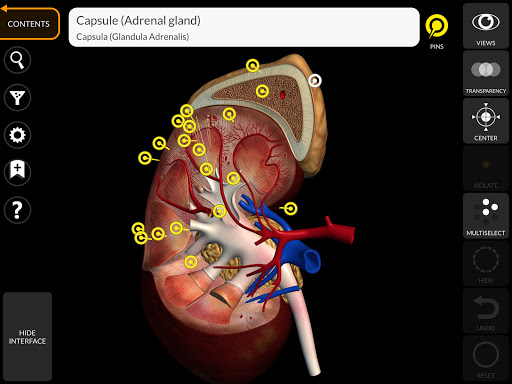

"Anatomía - Atlas 3D" permite estudiar la anatomía humana de forma fácil e interactiva.

A través de una interfaz sencilla e intuitiva es posible observar cada estructura anatómica desde cualquier ángulo.

Los modelos anatómicos 3D son especialmente detallados y con texturas de hasta una resolución de 4k.

La subdivisión por regiones y las vistas predefinidas facilitan la observación y el estudio de partes individuales o grupos de sistemas y las relaciones entre los diferentes órganos.

nervioso • Sistema respiratorio • Sistema digestivo • Sistema urogenital (masculino y femenino) • Sistema endocrino • Sistema linfático • Sistema ocular y auditivo CARACTERÍSTICAS • Interfaz sencilla e intuitiva • Rotar y hacer zoom en cada modelo en el espacio 3D • Opción para ocultar o aislar uno o varios modelos seleccionados • Filtro para ocultar o mostrar cada sistema • Función de búsqueda para encontrar fácilmente cada parte anatómica • Función de marcador para guardar vistas personalizadas • Rotación inteligente que mueve el centro de rotación automáticamente • Función de transparencia • Visualización de músculos a través de niveles de capas desde las superficiales hasta las más profundas • Al seleccionar un modelo o un pin, aparece el término anatómico relacionado • Descripción de los músculos: origen, inserción, inervación y acción • Mostrar/ocultar interfaz de usuario (muy útil con pantallas pequeñas) MULTILINGÜE • Los términos anatómicos y la interfaz de usuario están disponibles en 11 idiomas: latín, inglés, francés, alemán, italiano, portugués, turco, ruso, español, Chino, japonés y coreano • Los términos anatómicos se pueden mostrar en dos idiomas simultáneamente REQUISITOS DEL SISTEMA • Android 8.0 o posterior, dispositivos con al menos 3 GB de RAM Reversi